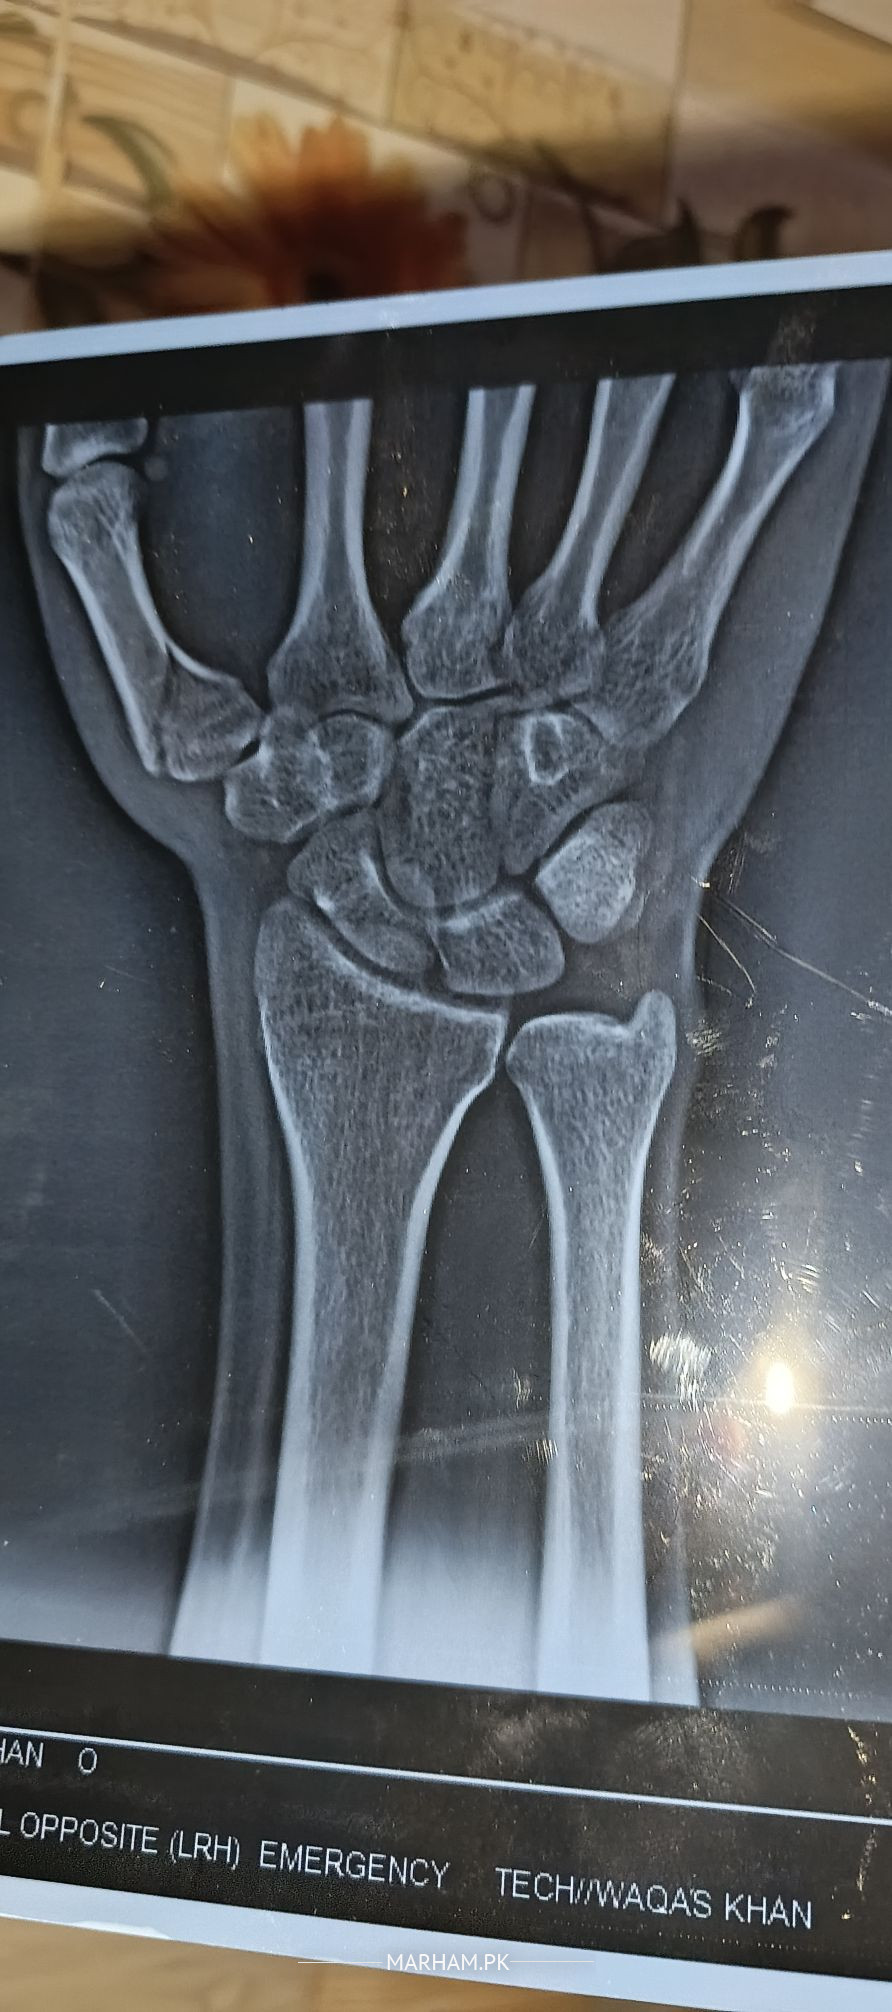

assalam u alaikum mera thumb 17 days pehle thoot gaya tha oer mene 15 days k leye plaster/cast lagaya leken mene ehtiat nahi ki per mene aj x ray leya to thumb ki halat wese ki wese hai. guide kare please kia karna chaheye

please apply pop again and keep it for 30 days.

Your thumb must be incorporated in the POP.

fracture is still not displaced.

it has acceptable position, However need to tailor the treatment plan according to patient need and dominance of hnad, profession etc nd I might fear you may have associated carple bone fracture.. scaphoid..?